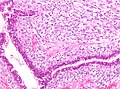

| LM | either (1) or (2): (1) large slit-like spaces, (2) cellular stroma - may be myxoid; +/-infiltrative border, +/-mitoses, +/-nuclear atypia, +/-"stromal overgrowth" ~ stroma fills microscopic field (see microscopic section) |

Microscopic

Features - either 1, 2 or both of the following:

- Large slit-like spaces - key feature. †

- Cellular stroma - key feature. †

- May be myxoid.

- +/-Infiltrative border.

- +/-Mitoses.

- +/-Nuclear atypia.

- +/-"Stromal overgrowth" ~ stroma fills microscopic field (see below).

Notes:

- † Large slit-like spaces are required for a benign phyllodes tumour.

- Slit-like spaces may absent in a borderline phyllodes or a malignant phyllodes.

- A cellular tumour without features suggestive of malignancy and without slit-like spaces is a cellular fibroadenoma.